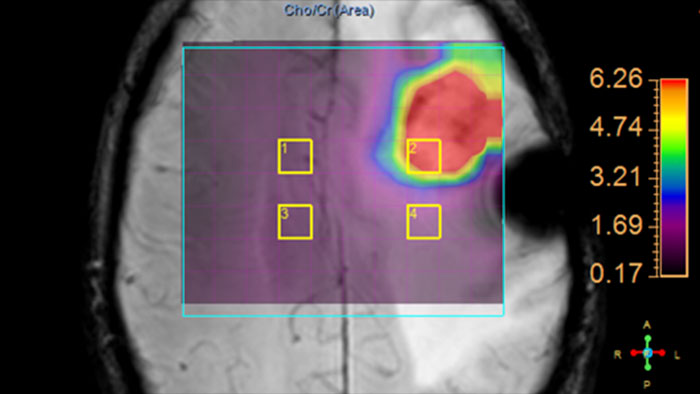

Review metabolite maps

MR SpectroView is a task-guided application providing hydrogen single voxel spectra as well as metabolic and ratio maps. It automatically identifies the anatomy to preselect appropriate metabolites or supports user-defined combination of metabolites.